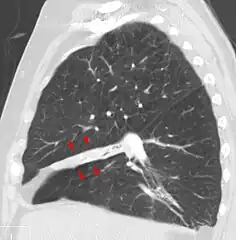

Atelectasis of a person's right lung

Clinically significant atelectasis is generally visible on chest X-ray; findings can include lung opacification and/or loss of lung volume. Post-surgical atelectasis will be bibasal in pattern. Chest CT or bronchoscopy may be necessary if the cause of atelectasis is not clinically apparent. Direct signs of atelectasis include displacement of interlobar fissures and mobile structures within the thorax, overinflation of the unaffected ipsilateral lobe or contralateral lung, and opacification of the collapsed lobe. In addition to clinically significant findings on chest X-rays, patients may present with indirect signs and symptoms such as elevation of the diaphragm, shifting of the trachea, heart and mediastinum; displacement of the hilus and shifting granulomas.[10]